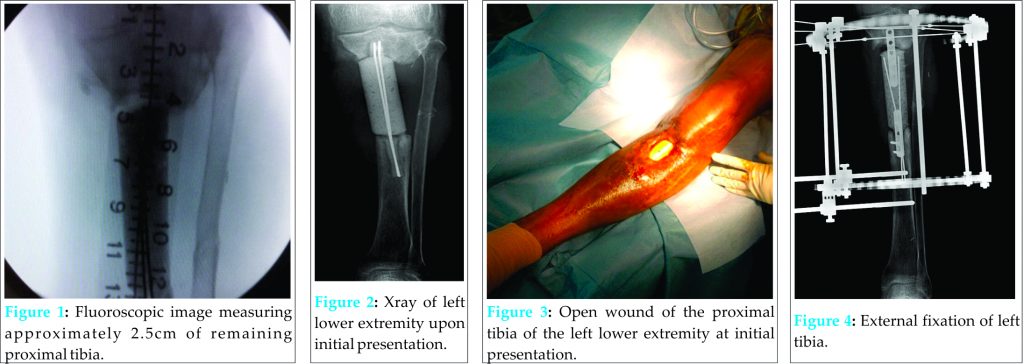

Osteomyelitis is an infection of bone tissue that may occur due to bacteremia, spread of local infection, or, as seen in this case, open fractures brought on by traumatic injury [4]. It has been estimated that as many as 50,000 hospital admissions occur each year due to osteomyelitis [6,3] and the mortality rate of this disease has been estimated to be about 2% [18]. Chronic osteomyelitis, which is characterized by infected dead bone and a prolonged, persistent infection, is particularly difficult to eradicate completely and often requires surgery [15]. Current treatment indications for this type of infection include debridement, aggressive antibiotic treatment, negative pressure dressings and skeletal stabilization (such as an external fixator) [3]. However, if these methods fail, amputation must be considered and may be preferable to recurrent operations and prolonged antibiotic treatment [4]. Lower-limb amputation is one of the most ancient and prolific surgical strategies employed to treat a wide array of ailments including infection, trauma, and cancer. It has been indicated in chronic osteomyelitis, particularly when multiple debridement operations and extensive antibiotic therapy have proven unsuccessful [4,3]. However, one of the major concerns regarding amputation involves post amputation function of the limb. Above knee amputations are known to significantly increase energy expenditure during the gait cycle and negatively impact rehabilitation when compared to below knee amputations [19]. Therefore, when considering amputation, it is important that the amputation be performed at the lowest level possible in order to preserve the maximum level of function and gait efficiency [19.4]. In this case, the patient R. A. would require an amputation in order to eliminate a very persistent and aggressive case of osteomyelitis of the left tibia secondary to open fractures of the left tibia and fibula. However, R. A. had acquired a segmental bone defect that left his proximal tibia at 2.5 cm (Fig. 1), which is too short to properly attach prosthesis post-amputation. When a post-surgical stump in a below knee amputation measures less than 3 cm, function of the limb is compromised and a below knee amputation is no longer feasible [5]. However, it was determined that a rotationplasty could be conducted in order to extend the length of the amputation stump and maintain a functional knee joint that would allow for the application of a prosthesis. Rotationplasty is a limb sparing technique that enables amputation of compromised lower limb tissue, while maintaining the functionality of the knee joint. During the classic rotationplasty, the knee joint is resected and the distal leg is rotated 180° and attached to the distal femur so that the ankle joint may serve as a functional knee joint after attachment of a prosthesis [4,3]. Rotationplasty is commonly indicated in osteosarcoma of the distal femur but has shown to be a useful alternative to above knee amputations in other limb salvaging strategies as well [4]. Our case report describes a rotationplasty of the distal bone and soft tissues of the leg that preserved the native knee, allowing for a below knee amputation of optimal length for a patient with chronic osteomyelitis of the midshaft tibia.

R. A. is a 51 y/o male with a history of uncontrolled, non-medicated diabetes and a 20 pack-year cigarette habit who presented to the emergency department on July, 17 2011 with fibrinous discharge from a 5 x 3 cm wound in the left lower extremity. The patient was involved in a motorcycle accident in 2009 in the Dominican Republic that resulted in open fractures of the left tibia and fibula. He subsequently underwent four surgeries in the Dominican Republic on the left lower extremity, including a surgery that involved placement of a plastic implant in the left proximal tibia (Fig. 2). After moving to the United States, R. A. presented to the Emergency Department after noticing opening of the operative site at the left proximal tibia and exposure of the plastic implant with associated discharge. Upon physical examination, R. A. was noted to have a 5 x 3 cm wound about the anterior aspect of the left proximal tibia. The wound extended through the associated soft tissues of the limb and a cement spacer implant, which was used to fill the bone void at the left tibia during a previous surgery in the Dominican Republic, was visible (Fig. 3).

Much of the anterior portion of the spacer was exposed to air. There was fibrinous exudate around the injured area but no frank erythema. Soft tissue examinations of the injured area demonstrated decreased attenuation and edema in the tibialis posterior muscle. It was noted that there was periostial new bone formation about the margins of the distal tibial fragment. Evaluation of the left fibula demonstrated non-unioned fracture in the proximal third fibular shaft. On July 20, 2011 R. A. underwent surgery on the left lower extremity, which included irrigation and debridement, intraoperative deep tissue biopsy, removal of the plastic spacer implant, insertion of antibiotic beads, and insertion of an antibiotic spacer at the site of the segmental defect of the proximal tibia. The segmental defect length was approximately nine cm, with the intact proximal tibia measuring 2.5 cm and the intact distal tibia measuring eight cm. A vacuum-assisted-closure skin graft was also placed on the open wound on the left lower extremity by the Plastic Surgery Department. Deep tissue biopsy cultures were positive for Klebsiella pneumoniae and Pseudomonas aeruginosa. Post surgery, R. A. was placed on zosyn (3.375g per IV every 6 hours) and vancomycin (1g per IV every 12 hours) antibiotic medication before being switched to meropenum (500mg every 6 hours) and vancomycin (1.25g every 12 hours) on July 23, 2011 as recommended by the Infectious Diseases Department. Over the next two years R. A.’s chronic osteomyelitis of the tibia was treated with irrigation and debridements and antibiotic treatments. On July 24, 2011, R. A. underwent surgery again which resulted in the replacement of his antibiotic spacer, irrigation and debridement, and the removal of his antibiotic beads. On July 26, 2011, R.A.’s antibiotic medication was changed to meropenum (1g every 8 hours). On July 28, 2011, another surgery was performed to exchange the antibiotic spacer, conduct another irrigation and debridement, and conduct a saucerization of the left tibia. On August 23, 2011, R. A. received another debridement and a split-thickness skin graft. On August 30, 2011, R. A.’s antibiotic treatment was changed to meropenum (2g every 8 hours). On August 31, 2011 R. A. received an Ilizarov-type hybrid external fixator to provide stability to the left tibia (Fig. 4). For several months, R. A. was able to ambulate with crutches without weight bearing on the left lower extremity, but R. A.’s chronic osteomyelitis remained persistent and his wound continued to drain. At this time, several long-term treatment strategies were discussed with R. A. as it was decided that he had an infection that could not be eradicated without amputation of the limb. Other modalities that were initially considered were the Papineau Technique and distraction osteogenesis. The Papineau technique is a type of open bone grafting technique in which wounds are packed with cancellous bone, usually for infected non-unions. However, this requires that the wound be clean and have adequate blood supply. In addition, the white count, ESR, and CRP should have normalized and the host has a normal immune system and adequate nutritional parameters. In addition, distraction osteogenesis after acute limb-shortening for segmental tibial defects has been shown have success [13] however, in the presence of chronic osteomyelitis it was not a viable option for patient R.A. However, despite multiple irrigation and debridements and prolonged course of antibiotics, the continued prescience of infection made the chance for success for those modalities low. Due to the short length of his native proximal tibia, a traditional below knee amputation was not a reasonable treatment option. Other levels considered were at the through knee and the above knee level, but there was concern for the loss of function and increase in energy expenditure that accompanies an amputation performed at these levels. After deliberation, consideration was given to a rotationplasty of the distal tibia to unite it to the proximal tibia and provide the patient with a below knee amputation of appropriate length. This would be the best option to provide definitive eradication of the infection while preserving the maximum knee function possible. On June 13, 2012, R. A. underwent surgery again to remove the taylor spatial frame from the left lower extremity, conduct an irrigation and debridement, and exchange the antibiotic spacer at the left proximal tibia. Another tissue biopsy from the left proximal tibia during this surgery showed growths of Methicillin-Sensitive Staphylococcus aureus. On June 18, 2012, R. A. received another irrigation and debridement and exchange of his antibiotic spacer. On June 21, 2012, a rotationplasty was performed on R. A.’s left lower extremity. Prior to the operation, R. A. was neurovascularly intact at the foot and ankle. First, R. A’s antibiotic spacer was removed without difficulty and the surgical incision was extended distally, while poor quality skin and fine extracts were resected. Dissection of the left ankle joint was then conducted from medial to lateral, exposing tendons and neurovascular bundles. The ankle joint was then disarticulated without difficulty and the distal tibia and fibula were exposed subperiosteally 1.5 cm proximal to the plafond. A supramalleolar osteotomy was made and exposure continued proximally while the tibia was dissected. Careful attention was paid to avoid injury to neurovascular bundles to ensure that adequate blood supply to the soft tissue remained intact. The distal tibia was then measured with the goal of providing about eleven cm of bone to the below knee amputation stump site Eight cm of distal tibia was then cut and dissected from associated soft tissue and significant scar tissue. Next, the proximal part of the dissected distal tibia was osteotomized at the level of the previous fracture with special attention paid to ensure that the posterior tibial artery remained intact to maintain good blood supply to the area. After the dissection was completed, the distal flap was then turned up to the proximal leg and the connection was held in place with multiple k-wires (Fig. 5, 6).Fluoroscopic evaluation revealed good alignment of the attachment site in coronal and sagittal planes. This attachment site was then secured using a proximal humeral locking plate held in place with a combination of locked and nonlocked screws on the medial side (Fig. 7, 8).